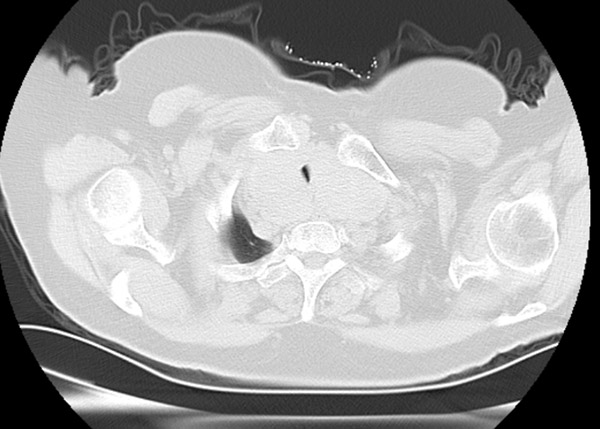

睡觉不能平卧,走路仅10步之内 患者石阿姨79岁,平时就气短乏力,反酸烧心,活动受限。近3个月症状加重,睡眠已经不能平卧,走路仅十步之内,严重影响日常生活。 石阿姨来沈阳市第十人民医院(沈阳市胸科医院)就诊,经检查后诊断为“胸骨后巨大甲状腺肿”、“食管裂孔疝”,胸骨后巨大的甲状腺肿压迫气管,导致气道严重狭窄, 呼吸困难。为解决石阿姨的痛苦,决定手术治疗,入住普外科后经完善检查,术前诊断结果很不乐观: 1. 胸骨后巨大甲状腺肿,气道狭窄;2.食管裂孔疝(Ⅲ型),胃食管反流病;3. 慢性阻塞性肺疾病(COPD);4.冠心病、高血压。 石阿姨高龄、肥胖且基础病多,影像学及内镜显示,声门下约2.5cm处气管出现长约3cm的严重狭窄,最窄处约3mm。甲状腺下极达主动脉弓以下,压迫双侧无名静脉及头臂干并向大血管间隙生长。麻醉和手术面临巨大风险。 多学科会诊,万全之策为手术护航 普外科向医务部提交多学科会诊,由麻醉专家庄晓晨副院长牵头组织普外科、麻醉科、胸外一科、呼吸二科、心脏中心各位专家进行科学严谨的全面评估,多学科会诊意见:要想解除气道狭窄缓解呼吸困难,只有手术切除甲状腺肿,食管裂孔疝二期处理,并制定了围手术期治疗措施及详细的麻醉、手术预案。 麻醉科根据此患者特殊情况拟定两种麻醉方案, 方案一:局麻下行气管镜探查,如狭窄处条件允许,则清醒状态下置入合适管径插管后予以全身麻醉。 方案二:如气管镜探查狭窄处口径过窄,无法置入合适气管插管不能满足通气需要,则行ECMO(体外人工膜肺)辅助下全麻手术,即于左右股静脉分别置入一根导管至下腔静脉与右心房处,将患者静脉血从下腔静脉抽出后经氧合器氧合再泵入右心房的方式来代替肺脏工作,从而达到无需气管插管又能满足机体氧供的效果。 普外科也制定了手术预案:1.甲状腺肿巨大,同重要血管神经关系密切,术中精细解剖,逐次支持切除,避免血管损伤至大出血,并要求快速切除病变解除气道压迫。2. 如逐次支持不能切除甲状腺肿,行劈开胸骨切除或胸腔镜下解剖游离甲状腺下极。3.气管长期受压,有气管软化可能,切除甲状腺肿可致气管塌陷,如不能悬吊支持气管,行气管切开气管套管置入。与患者及家属充分沟通并告知风险后,其表示十分理解与信任并坚决要求在我院行手术治疗。 巨大甲状腺肿2小时全切除,气道压迫完全解除 手术当日,麻醉科主任王涛、副主任医师张祥超等麻醉团队将各种型号导管、紧急气道装置、ECMO设备准备就绪,虽然插管过程困难,但最终在患者清醒状态局麻下经气管镜将较细的6.5#插管成功送至狭窄处远端后予以全身麻醉,连接呼吸机管路顺畅,压力适中且氧合良好。普科主任陈晓峰、副主任医师王鑫、主治医师刘聪手术团队在手术室护理团队的配合下,精细解剖、逐次支持切除,2个小时完成胸骨后巨大甲状腺肿双侧次全切除,完全解除气道压迫。术后第一天,阿姨下床活动行走自如,5天出院,彻底告别了不能平卧、轻微活动就呼吸困难的生活。 这例手术的成功,体现了医院多学科团队鼎力协作的专业风采。在ECMO技术支持保障、充分术前预案的基础上,即便面对复杂的疾病,也有确切实力为越来越多的患者解除病痛。 在沈阳市第十人民医院(沈阳市胸科医院),医者不仅有严谨的专业能力,更有为患者解除病痛的信念,与病魔做斗争、与患者同呼吸,为更多家庭造福。 供稿:普外科 普外科 科室简介: 沈阳市第十人民医院(沈阳市胸科医院)普外科为集医疗、科研、教学为一体的综合性临床科室。主要收治甲状腺、颈部肿物及乳腺疾病,肝胆胰脾、胃肠、肛门疾病,食管裂孔疝、腹外疝等,疾病涵盖感染、肿瘤及创伤等。以微创治疗为主要治疗手段,患者创伤小,恢复快。 联系电话:88323438转8228 地址:沈阳市第十人民医院 一号楼10层